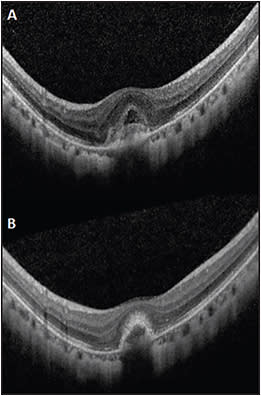

Fluorescein angiography (FA) is indicated to confirm the diagnosis of myopic CNV before starting anti-VEGF treatment. Spectral-domain optical coherence tomography (SD-OCT) is also very useful for assessing myopic CNV (Figure 1) and for documenting any coexisting macular changes, such as myopic traction maculopathy or myopic foveoschisis. Both the RADIANCE and MYRROR studies adopted a PRN treatment approach after the initial injections for retreatment. During reassessment, VA, symptomatology, and SD-OCT findings are useful to determine if retreatment is needed. In cases where SD-OCT appears “dry” but is accompanied with visual loss, FA should be considered because fluorescein leakage may be a more sensitive indicator of residual activity in eyes with myopic CNV.